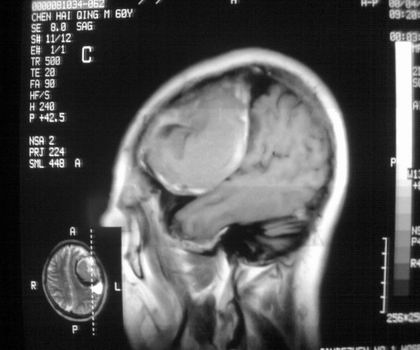

以下是引用影像孺子牛在2008-4-29 21:20:00的发言:[br]首先病变定位在脑外,根据ct密度及mri信号特征考虑慢性硬膜下血肿不连续环形钙化。

以下是引用周战梅在2008-4-29 23:12:00的发言:[br]脑外病变,蛛网膜下腔增宽,囊壁点状、环形钙化,增强扫描呈不均匀环状强化,考虑为囊性脑膜瘤可能性大,慢性脓肿、血肿机化、胆脂瘤不能除外。